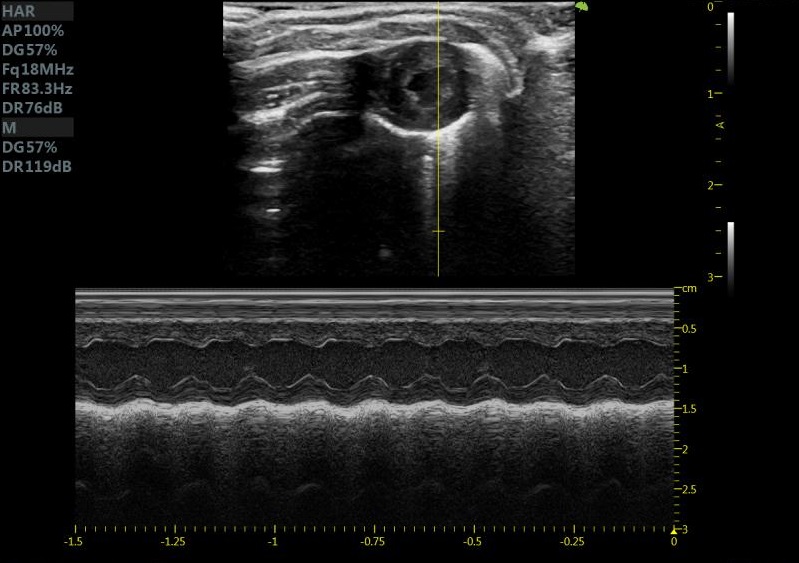

齐全的功能模块 :心脏测量包

小鼠长轴M型 小鼠短轴M型

小鼠长轴B型 小鼠短轴B型